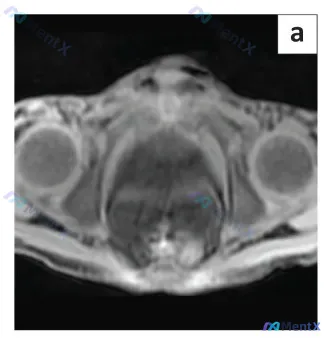

今天整理资料时看到一个挺有警示意义的案例,先不说是哪个科室的,先看思路—— 起初拿到的信息是“眼部MRI”,但第一眼看到图像就觉得不对:解剖结构完全对不上。图像中央是一个盆腔脏器,膀胱底在前方,直肠在后方,两侧还有对称的股骨头——这明明是男性盆腔的轴位图像,核心展示的是前列腺区域。 这个“标签错位”...